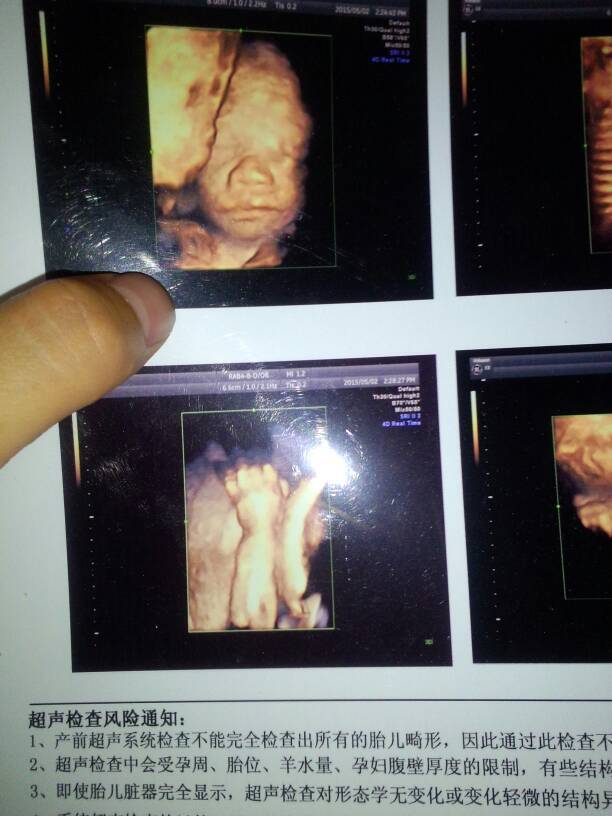

四维归来,感觉女儿的四维照片怪怪的,头部疙疙瘩瘩的,这是什么原因那 四维归来,感觉女儿的四维照片怪怪的,头部疙疙瘩瘩的,这是什么原因那 点击展开 幽林洞箫 2015-05-04 15:13 为您推荐: 其他回答 没事!!!双子吗! 诺言_BUkg 2015-05-04 16:09 你好,根据您所说的情况,这是思维拼图大概的人形,真正的宝宝要比四维照片上漂亮多了。 依一望 2015-05-04 15:57 还没开始长脂肪,皮是皱的 小珂馨妈咪 2015-05-04 15:37 这个时候又不能看出什么 @Angel@ 2015-05-04 15:28 彩超设备不好,照不清 看看星星 2015-05-04 15:22 加载更多 相关问题 四维彩超照片怎么疙疙瘩瘩的!是什么? 怀孕6个月做四维检查照片上胎儿头部像有肿瘤样的,凹凸不平是什么原因?请各位指教一下 宝宝的第一张照片,为什么现在四维彩超没有全身照,只有头部照片啊?你们也是吗?